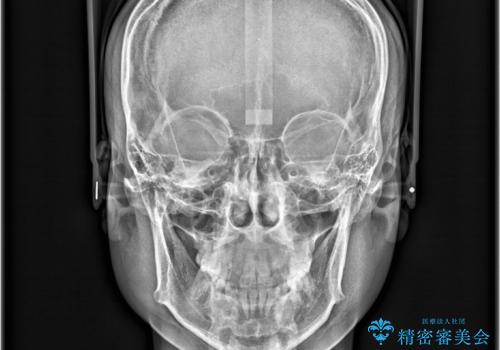

非抜歯矯正で八重歯を改善|短期間8か月で美しい歯並びに|インビザラインライト上顎のみで矯正

- 「八重歯を治したい」との主訴でご来院された患者様です。。

非抜歯で上顎のみインビザラインライトを使用して矯正を行いました。

短期間(約8か月)の治療で歯並びが整い、患者様も大変喜ばれました。